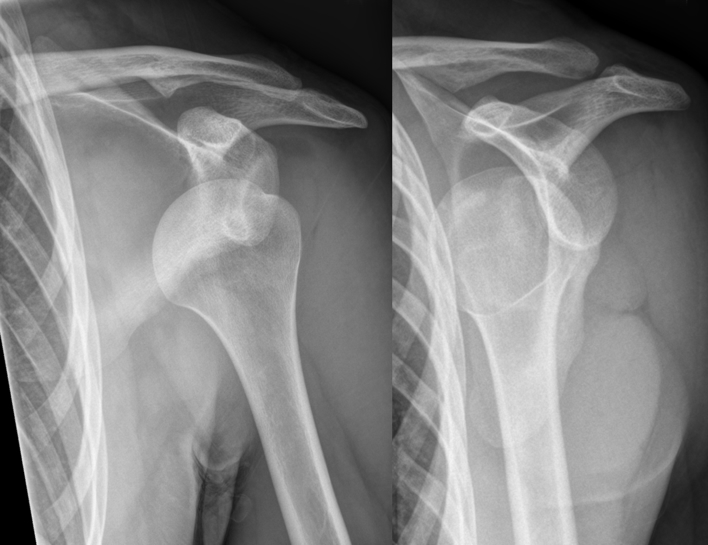

Dislocations and Nerve Injury Risks

- Shoulder Dislocation (Glenohumeral):

- Axillary nerve

- Musculocutaneous nerve

- Radial nerve

3. Hellerhoff, CC BY-SA 3.0 <https://creativecommons.org/licenses/by-sa/3.0>, via Wikimedia Commons

| Axillary | Shoulder dislocation | Loss of shoulder abduction (deltoid) | Skin over deltoid region |

| Musculocutaneous | Axilla | Weak elbow flexion | Lateral forearm |

| Radial (Axilla) | Axilla | Wrist drop; ↓ elbow extension | Posterior arm, forearm, hand dorsum |